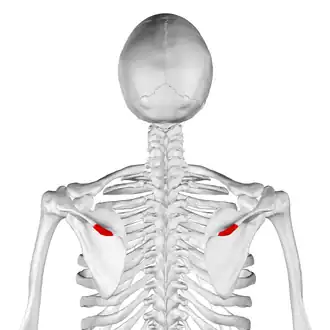

Posterior view. Deltoid tubercle shown in red. | |

The deltoid tubercle of spine of scapula is a prominence on the spine of scapula. The spine, at lateral to the root of the spine, curves down and laterally to form a lip.[1] This lip is called the deltoid tubercle.

Middle and inferior fibres of trapezius muscle, and deltoid muscle, attached to the deltoid tubercle.[1][2] The deltoid tubercle marks the beginning of attachment of deltoid muscle.[1]